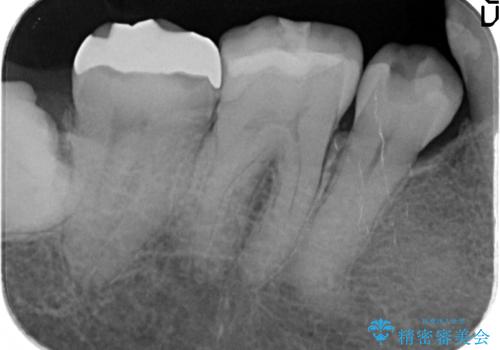

- 昔治療した奥歯の見た目が気になるのでセラミックでやり直したいといらっしゃった方の症例です。

右下6、7の古い詰め物および虫歯を除去後、オールセラミッククラウンによる補綴を行いました。